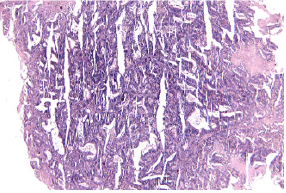

IN 1999, When the patient was 37, a cancer of the uterine cervix debuted (stage IA2), and the patient had total hysterectomy. In 2003, a neoplasm of the ovary was diagnosed and treated (Pathology result: endometrioid adenocarcinoma, grade II), for which bilateral adnexectomy and omentectomy were performed. Further on, the patient pursued chemotherapy. In 2017, a rectal cancer (pathology report: moderately differentiated mucinous adenocarcinoma), was diagnosed for which the patient received radiotherapy and, after that, abdomino-perineal resection. In June 2020, the patient presents with a bleeding vaginal tumor, relapse from the ovarian cancer (Pathology exam: tumor with aspects of papillary adenocarcinoma). The procedure performed was radiofrequency ablation for haemostasis . In September 2020, the patient presents with an enteral- vaginal fistula secondary to a non- resectable pelvic relapse, a block communicating with the small bowel loops and further on with the vagina, with a vaginal discharge of small bowel content of approx 1L/day.

The surgical intervention performed was an internal digestive derivation (ileal-caecal anastomosis) and exclusion ligations of the fistulised loop. After the operation, a fistula of the ileal-caecal anastomosis occurred with faecal peritonitis. In an emergency setting, due both to the nature of the disease and to systemic infection signs, reoperation was performed, and an ileostomy was performed (Figures 1-8) [1].